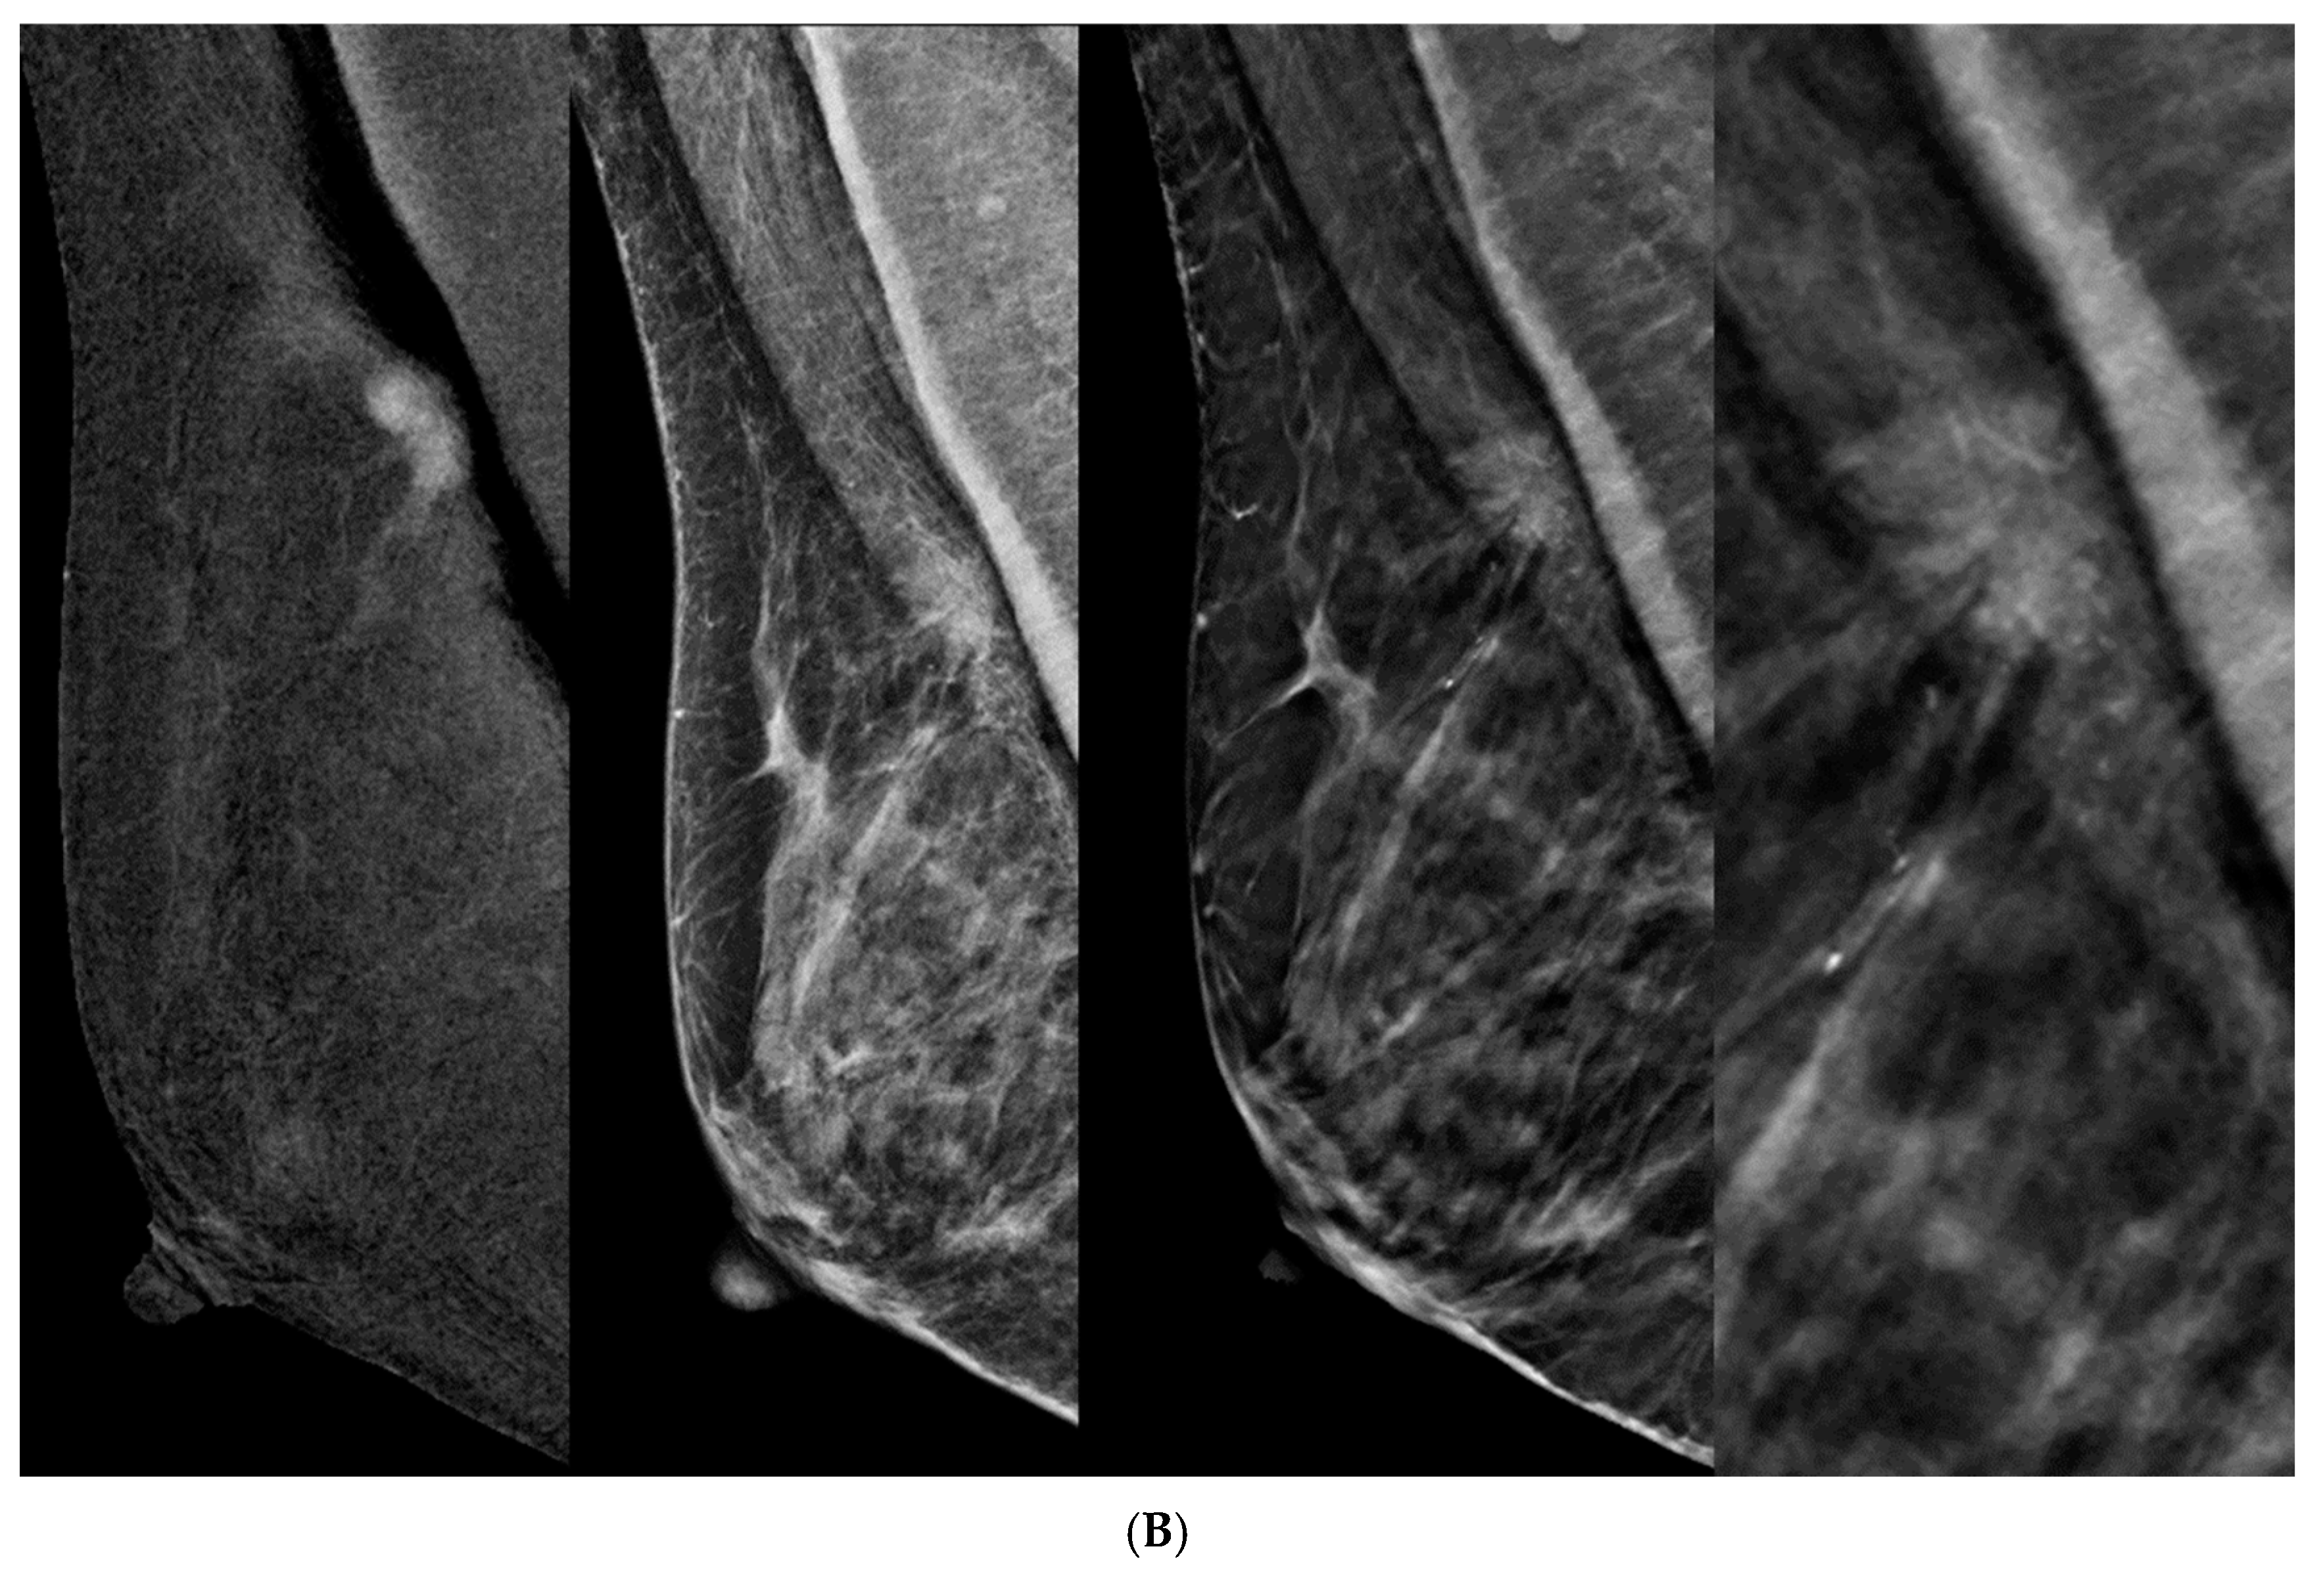

- Incorporating DBT into CEM-detected lesions leads to a significant upgrade in BIRADS scores toward the lesion’s true pathology (p > 0.0001).

- This was consistent across all readers, with particularly notable differences observed among less experienced readers.

- The primary driver for the score upgrade was attributed to improved margin visibility facilitated by DBT.